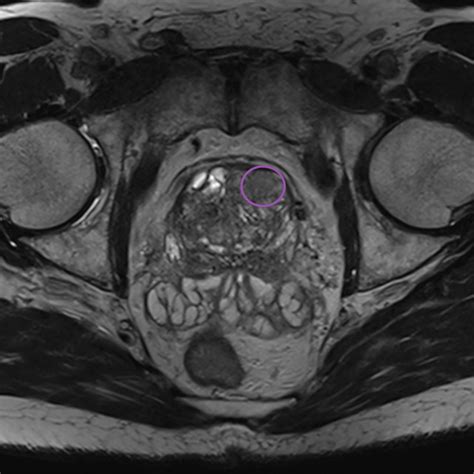

When a patient is assigned a Pi Rads 4 score, it means that there is a well-defined lesion on the MRI that exhibits characteristics highly suggestive of a potentially aggressive tumor. Specifically, for peripheral zone lesions, this means a focal, low-signal intensity lesion on T2-weighted imaging and marked diffusion restriction on Diffusion-Weighted Imaging (DWI). For transition zone lesions, it refers to a lenticular or non-circumscribed, encapsulated, moderately hypointense lesion.

Once a Pi Rads 4 lesion is identified, the standard protocol typically involves a fusion biopsy. This procedure combines the real-time ultrasound imaging used during the biopsy with the previously taken MRI scan. By "fusing" these images, the urologist can accurately guide the biopsy needle directly into the suspicious area identified as Pi Rads 4 on the MRI. This technique is significantly more accurate than traditional, random biopsies, which may miss small or localized lesions.